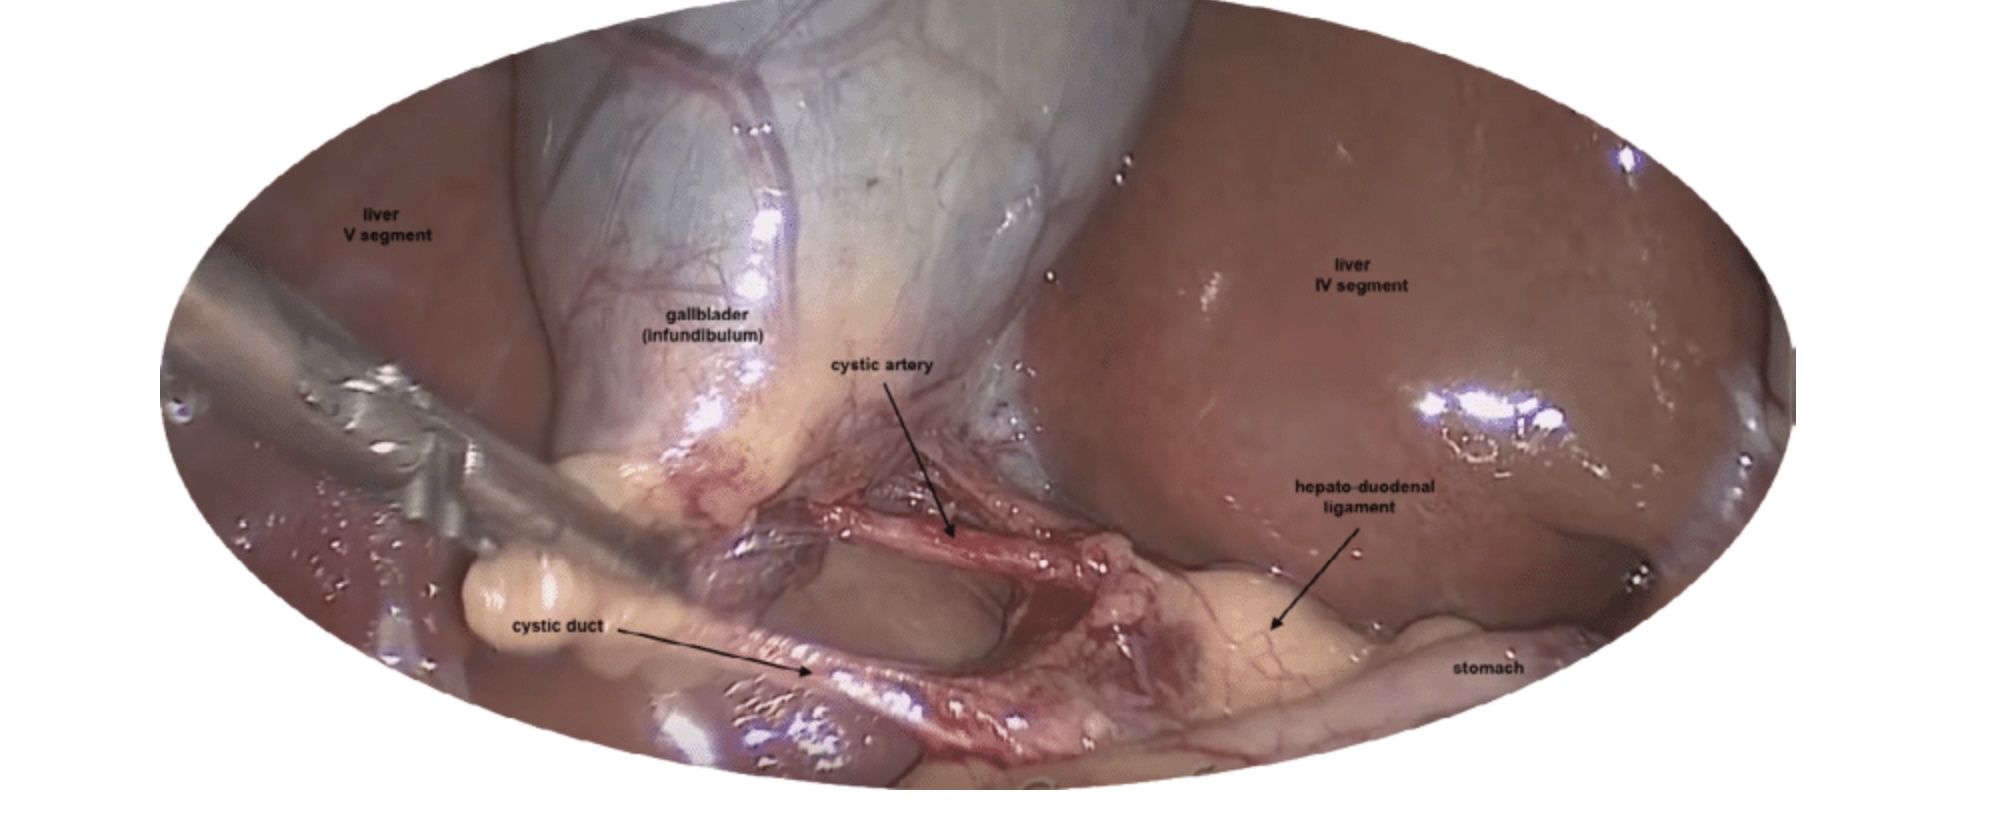

For most patients, laparoscopic cholecystectomy is the recommended treatment. This minimally invasive procedure involves:

• Tiny incisions instead of a large open cut.

• Use of a camera and specialised instruments.

• Commitment to Safety & Low Complication Rates: My surgical practice is built on meticulous technique and decision-making, aiming for the lowest possible complication rates. This includes a specific focus on minimising risks such as bile duct injury.